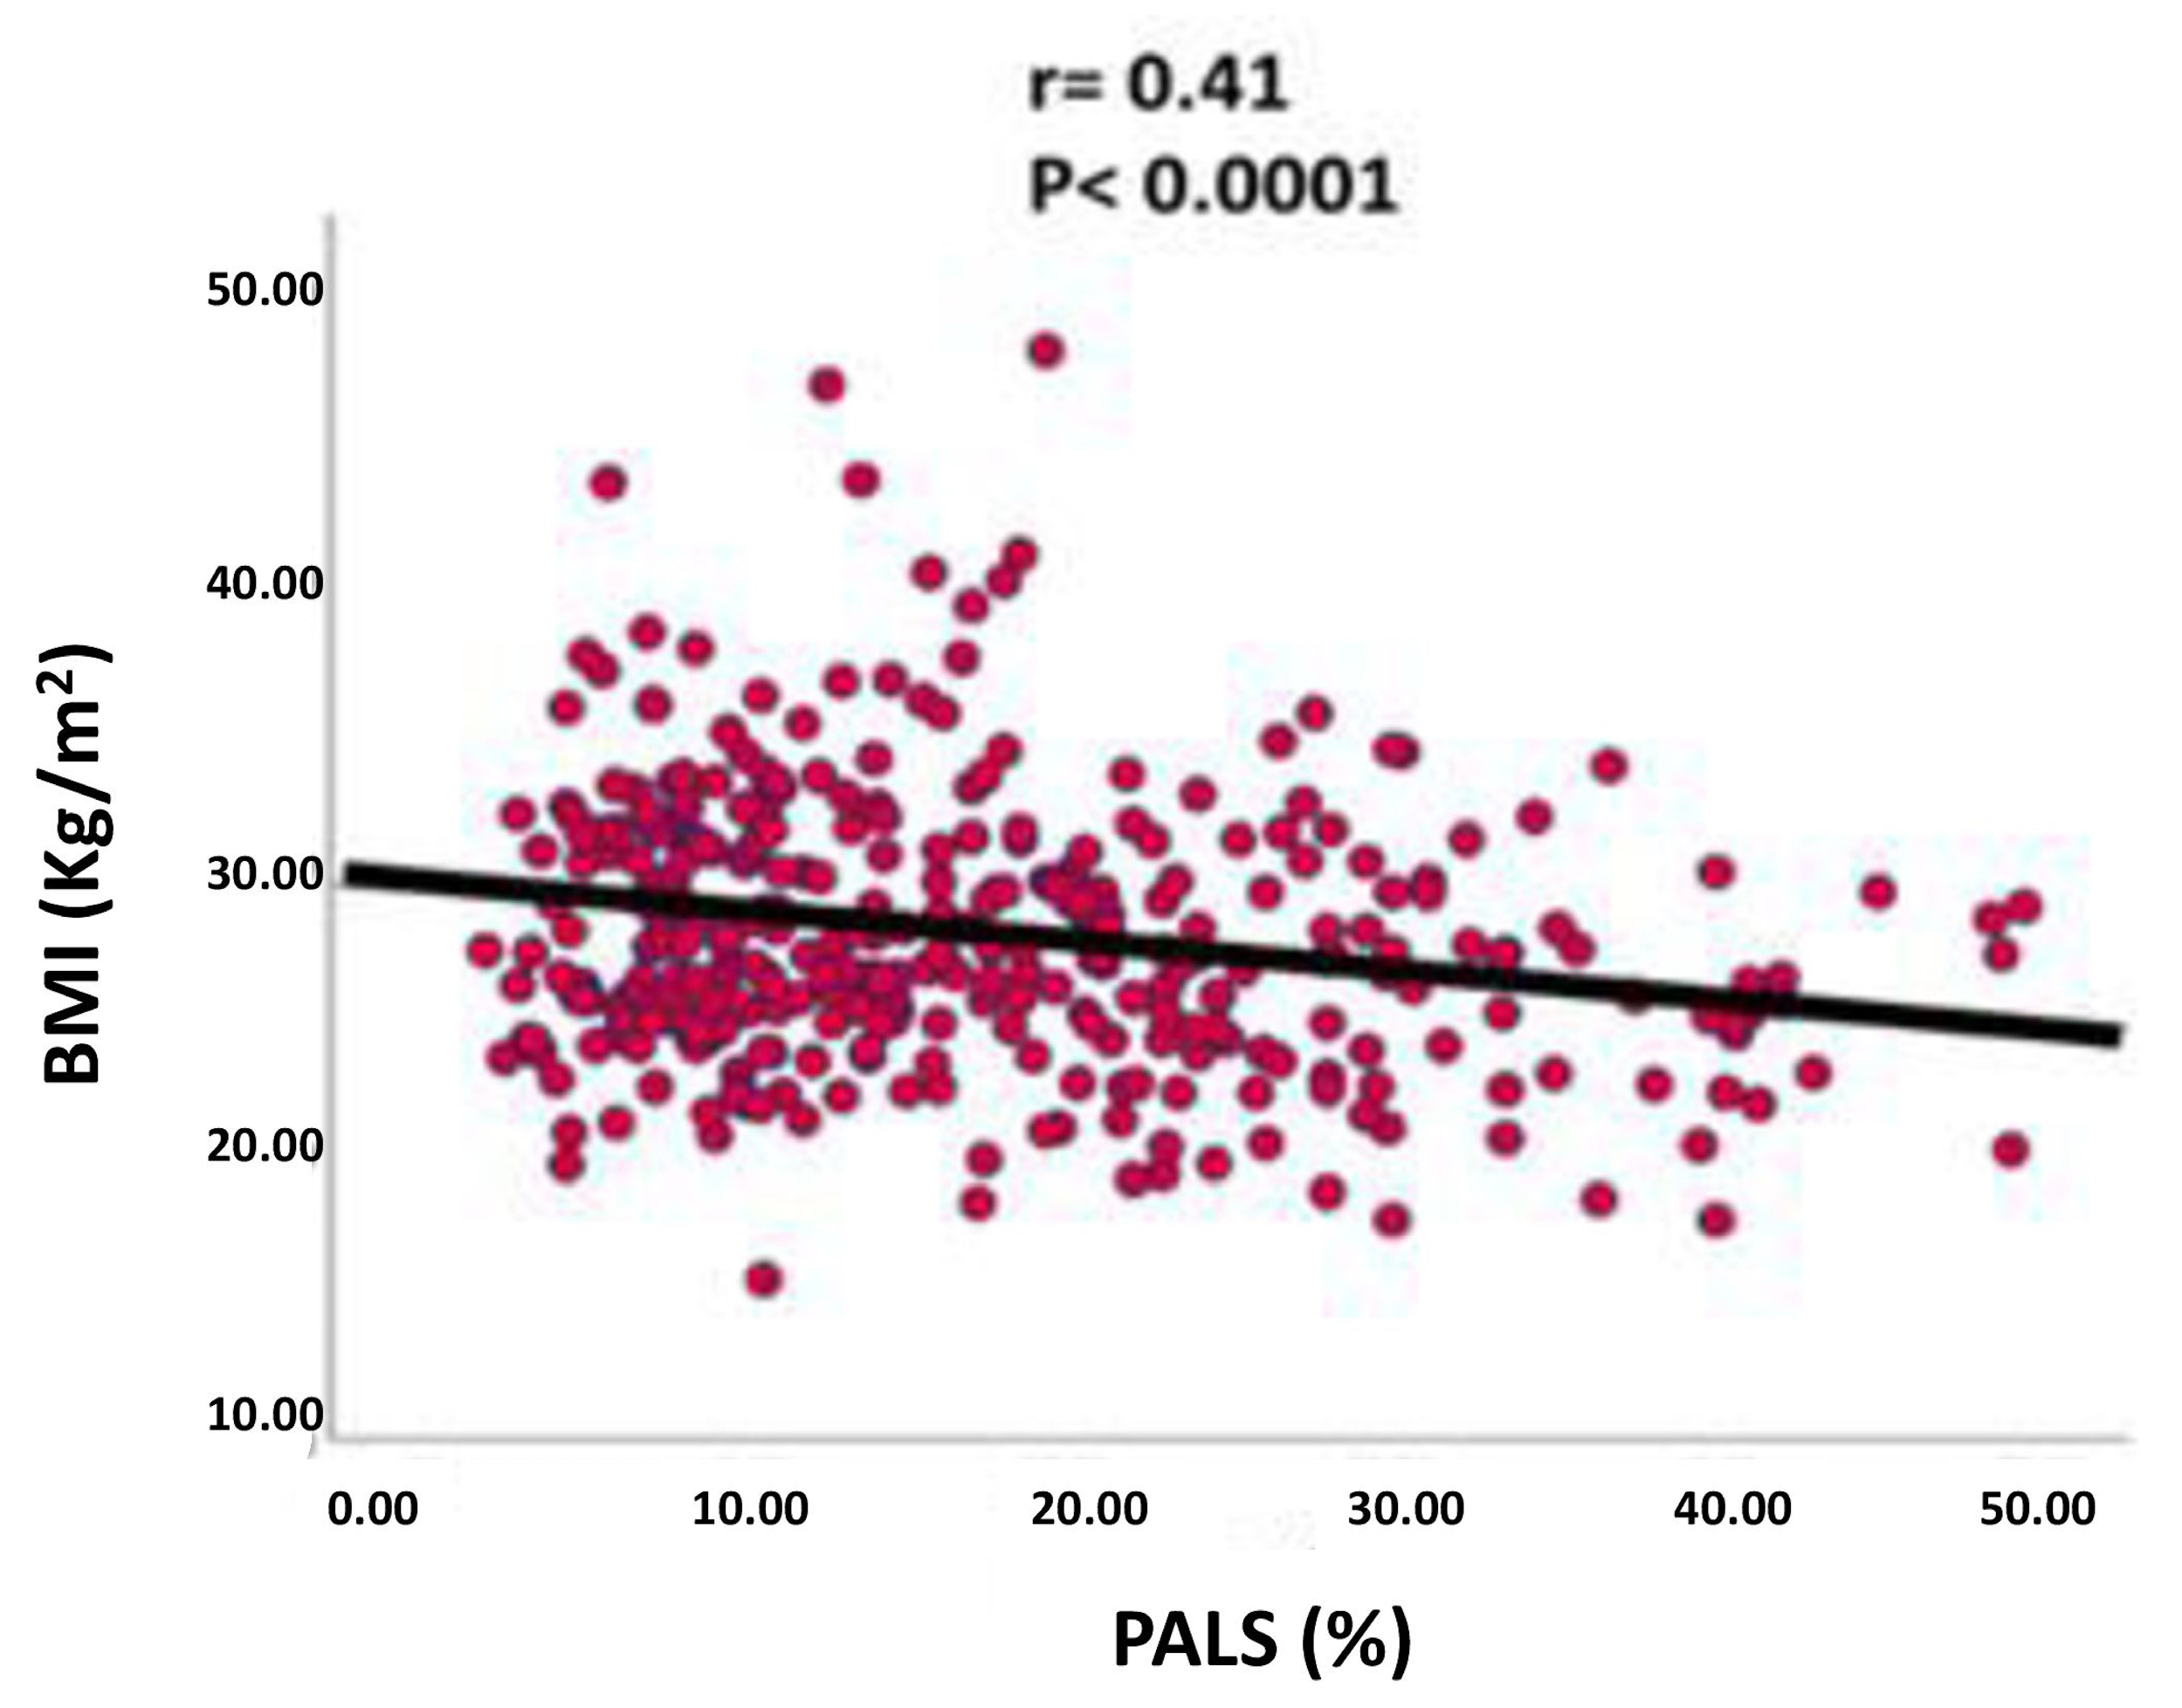

- Peak atrial longitudinal strain (PALS), measured at the end of the atrial reservoir phase. Which in normal subjects is greater than 40%. In patients with atrial fibrillation it has been seen that the reduction in strain reflects structural alterations of the left atrium (wall fibrosis) [36] (Figure 2)

| PALS (%) | 19.0 ± 11.5 | 17.8 ± 10.6 | 14.2 ± 8.3 | NS | 0.03 | 0.02 |

| PALS | CHA2DS2-VASc | −0.180 | <0.001 |

| LV mass index | −0.112 | 0.04 | |

| LV EF | 0.228 | <0.0001 | |

| E/e’ | −0.141 | <0.01 | |

| PAPs | −0.153 | 0.006 | |

| BMI | −0.140 | 0.004 |